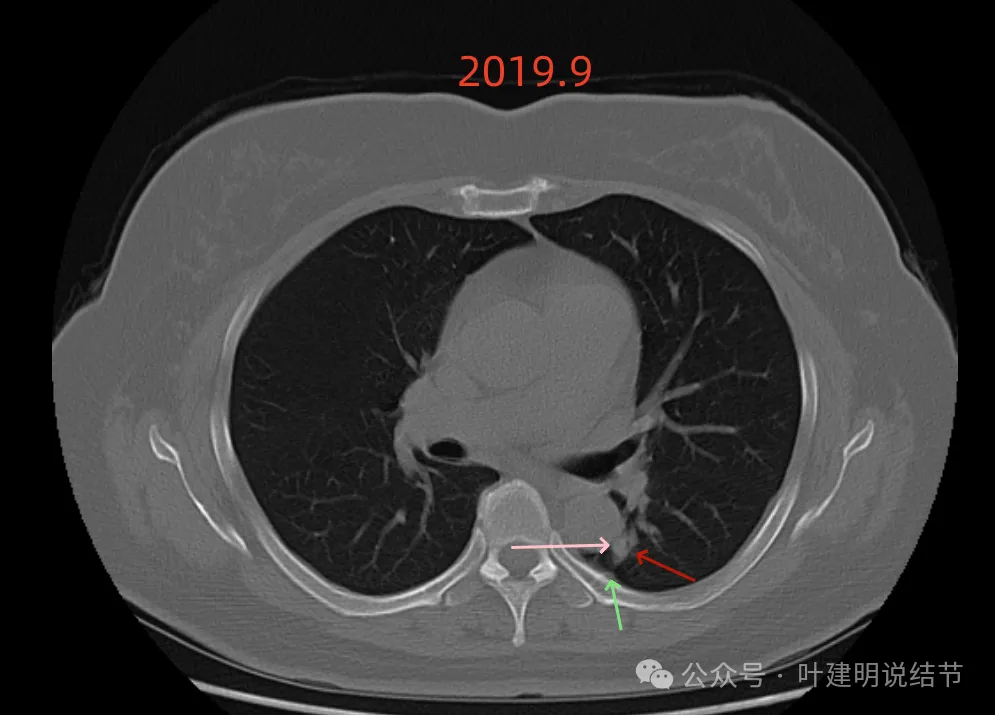

先看2019年时的影像:

病灶出现,密度不纯,有点状高密度成分,表面不光滑不平整。

实性成分为主,但边缘缺乏膨胀性,长刺较细长,感觉更像慢性炎。

此层不是很像炎症,有一定膨胀性。黄色箭头处示有细支气管被病灶截断似的;紫色箭头示略有小的毛刺征;但绿色箭头所指的胸膜有增厚的表现,而且蓝色箭头指的条状不锐利,这又与炎性病变并影响邻近胸膜是符合的。

上图密度较高,大部分实性,灶内略杂乱,与主动脉壁之间稍有缝隙,对应胸膜略有增厚,整体轮廓较清。

这样的病灶首次发现,虽不能完全除外恶性,但慢性炎的解释相对更符合些,肯定是要先随访观察或消炎后复查再对比。